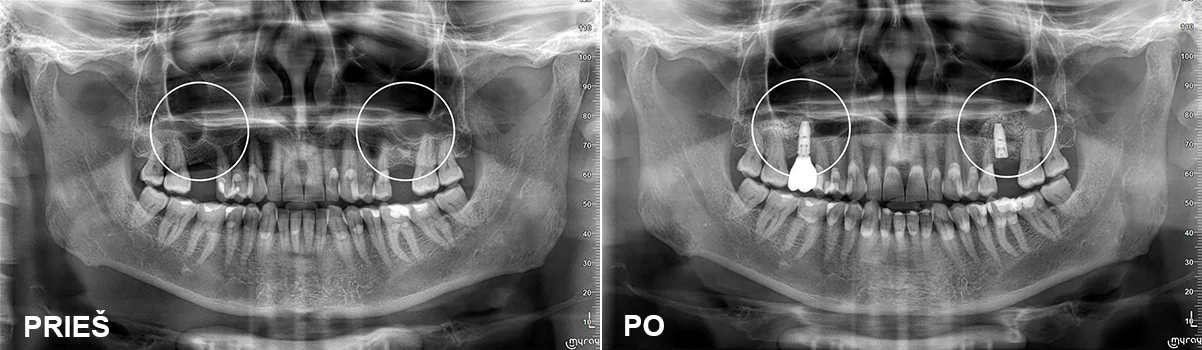

Sinuso pakėlimo procedūra

Pacientas buvo jau senai netekęs dviejų krūminių dantų. Kaulo aukščio stabiliems implantams nepakako, todėl buvo atlikti abiejų pusių sinuso pakėlimai ir tos pačios operacijos metu įsriegti dantų implantai. Po šešių mėnesių implantai suprotezuoti cirkonio keramikos vainikėliais.

Protezavimas – gyd. Kristina Gegeckaitė

Klinika „Ortodenta“